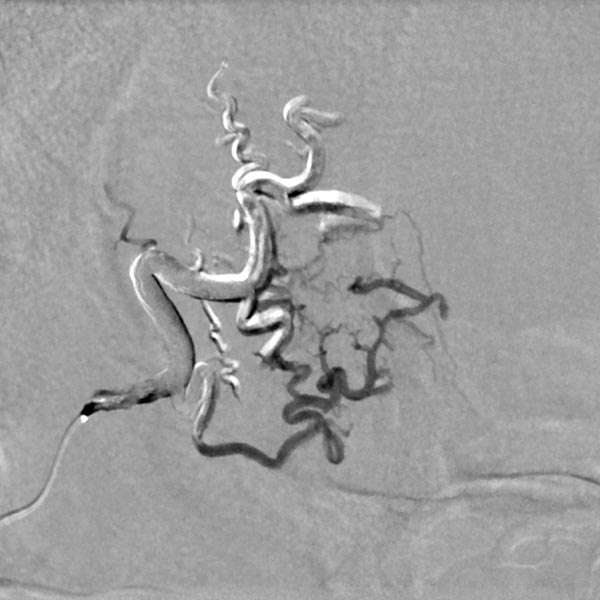

Die digitale Subtraktionsangiographie (DSA) über rechte die Arteria carotis externa und die Arteria temporalis superficialis zeigt eine feinfistulöse AVM mit deutlich dilatierten Feederarterien an der rechten Stirn und sofortigem venösen Abstrom.

Der Mikrokatheter wurde bis direkt zum Nidus vorgebracht. Nach Darstellung des Nidus sofortiger, direkter venöser Abstrom (DSA, venöse Phase) aus der Läsion über dilatierte Venen. Dies sichert die Diagnose einer AVM.

DSA-Bild mit Darstellung des gesamten arteriellen Einstroms, des Nidus und des venösen Abstroms der AVM vor der Embolisation. Die Angioanatomie der hier noch unbehandelten AVM ist klar erkennbar.